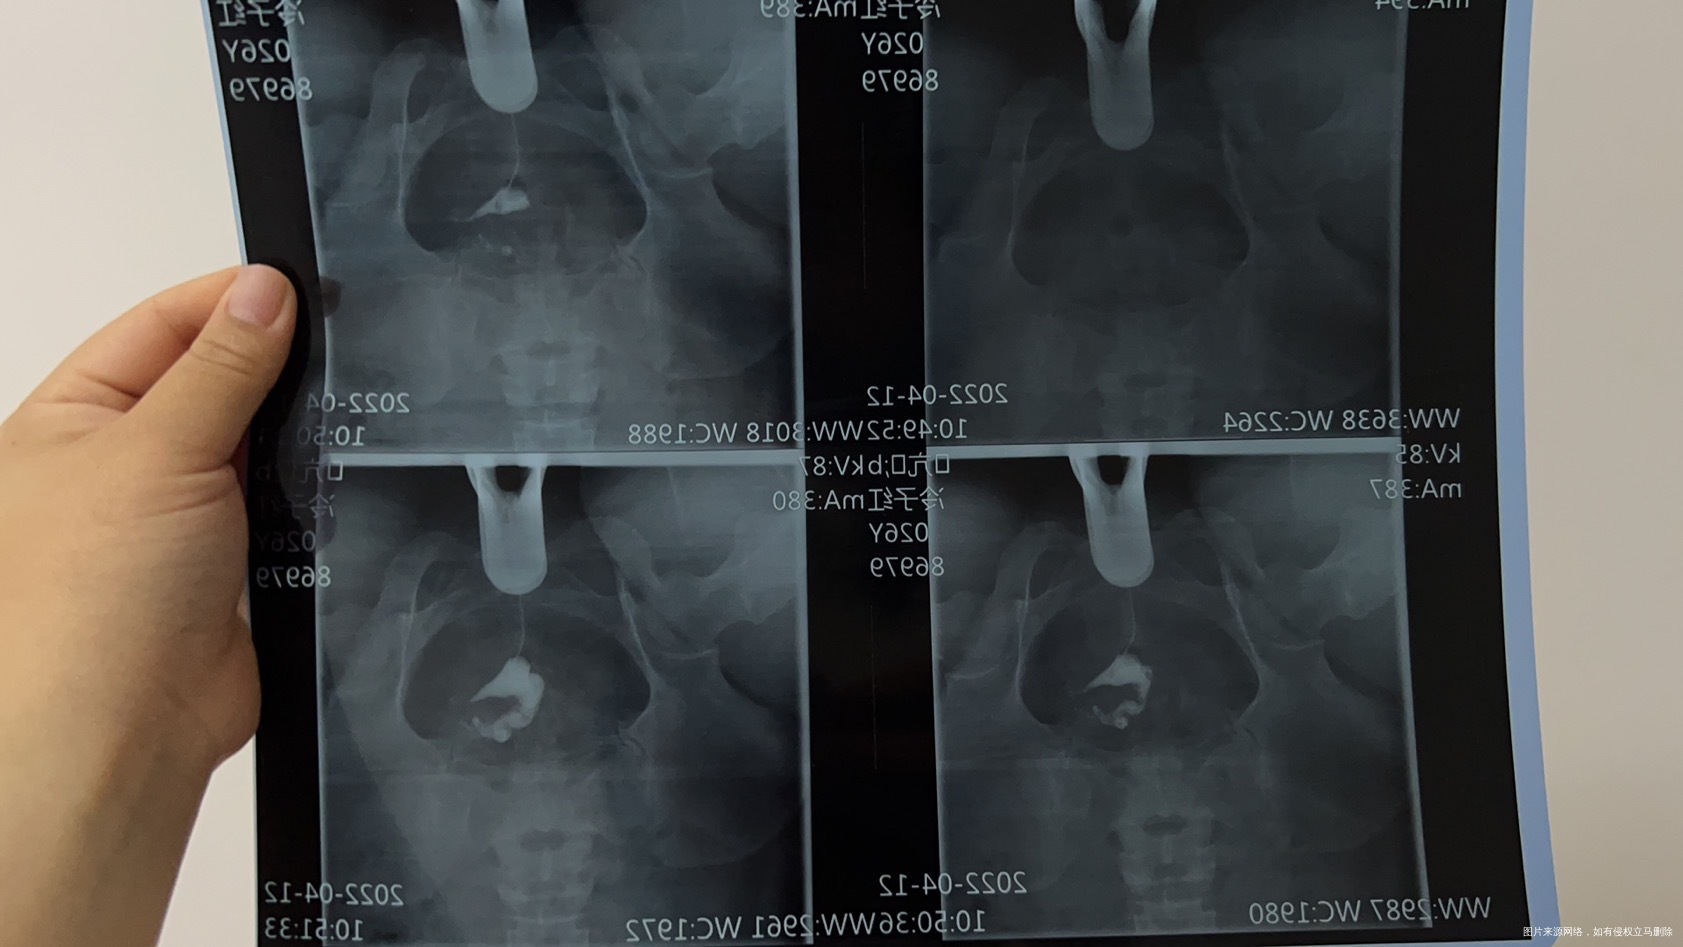

我去检查了输卵管 一边积水 一边堵了 我想知道做试管用不用先把积水取出来

您好,这种情况只能选择试管助孕,建议您拿着检查报告去当地生殖中心进行评估,如果积水严重,最好还是先处理后再进行试管,积水回流容易影响胚胎着床。